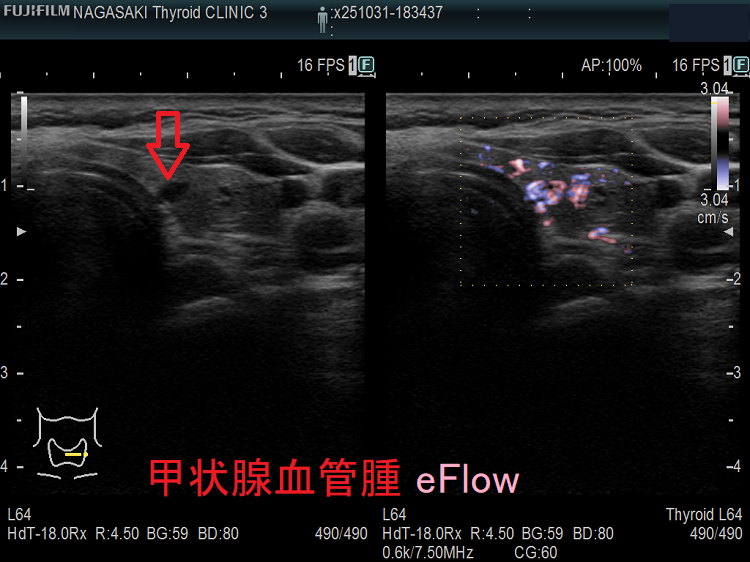

甲状腺に発生する血管腫は非常に稀で、日本の報告例もわずかです(日臨外会誌 72(3),579―583,2011)。

ケース①

ケース②

ケース③

甲状腺血管腫(拡大) ドプラーモード(eFlow);腫瘍内血管が3次元的に見え、毛玉の様。

ケース④